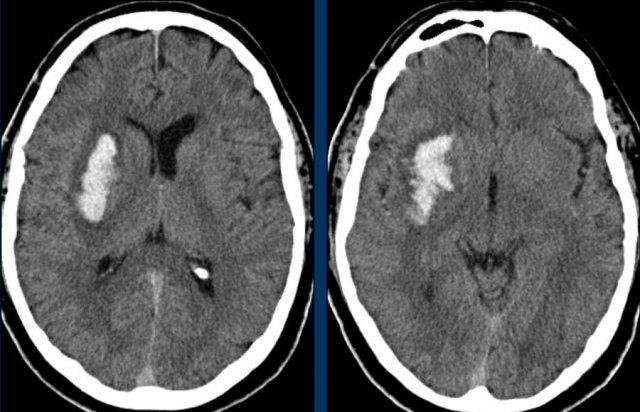

Các hình ảnh cho thấy xuất huyết do tăng huyết áp điển hình tại nhân bèo (putamen), là phần lớn nhất và nằm ngoài cùng của hạch nền.

Tiếp tục xem các hình ảnh theo dõi…

Trên phim chụp theo dõi, chỉ thấy mất nhu mô tại nhân bèo – nơi xuất huyết đã xảy ra (mũi tên).

Nhân bèo được cấp máu bởi các động mạch thấu kính-vân (LSa).

Các LSa là các mạch tận cùng có đường kính nhỏ, xuất phát từ động mạch Charcot theo góc vuông, không có sự giảm dần kích thước như ở các mạch vỏ não xa.

Áp lực nội mạch của chúng có thể rất cao và vì lý do này, các LSa đặc biệt dễ bị tổn thương do tăng huyết áp, hình thành các vi phình mạch và vỡ mạch (3) (tài liệu tham khảo).

Ba hình ảnh đầu tiên cho thấy khối tụ máu lớn tại hạch nền bên phải kèm phù não lan rộng.

Hình ảnh theo dõi một năm sau cho thấy hình ảnh hang hóa dạng tuyến tính do mất mô (mũi tên) và giảm tỷ trọng hạch nền là hậu quả của xơ hóa thần kinh đệm (gliosis).